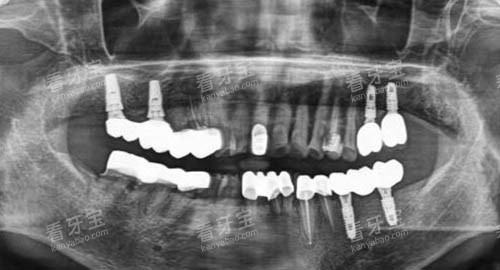

在口腔种植方面,北京禾禾口腔的医生们凭借优质的技术和丰富的经验,为患者成功植入了大量的种植牙。

这些种植牙不仅外观逼真,而且功能强大,能够像真牙一样正常咀嚼和使用,为患者解决了牙齿缺失的困扰。